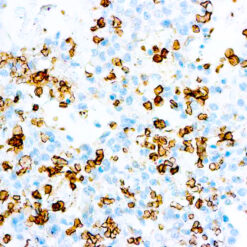

Cytokeratin (CAM5.2)

Anti-Cytokeratin (CAM 5.2) reagent has a primary reactivity with human keratin proteins that correspond to Moll’s peptides #7 and #8, Mr 48 and 52 kilodaltons (kd), respectively. Cytokeratin 7 and 8 are present on secretory epithelia of normal human tissue but not onstratified squamous epithelium. Anti-Cytokeratin (CAM 5.2) stains most epithelial-derived tissue, including liver, renal tubular epithelium, and hepatocellular and renal cell carcinomas. Anti-Cytokeratin (CAM 5.2) might not react with some squamous cell carcinomas.

| Cellular Localization | Cytoplasmic |